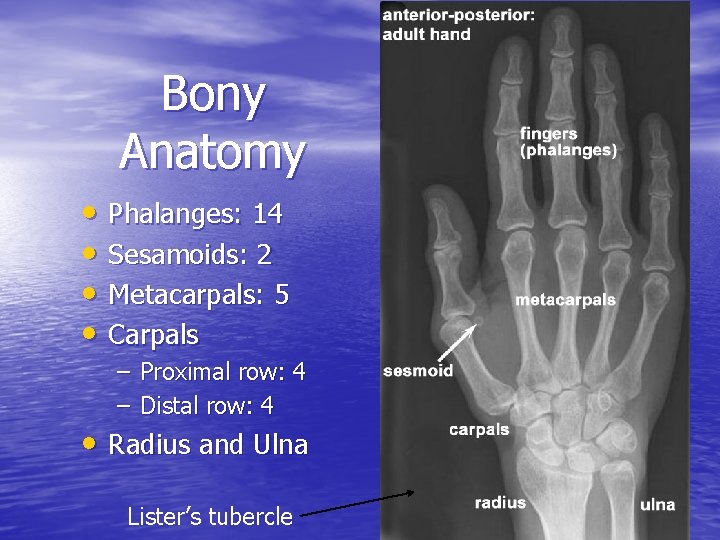

Bony Anatomy • Phalanges: 14 • Sesamoids: 2 • Metacarpals: 5 • Carpals – Proximal row: 4 – Distal row: 4 • Radius and Ulna Lister’s tubercle